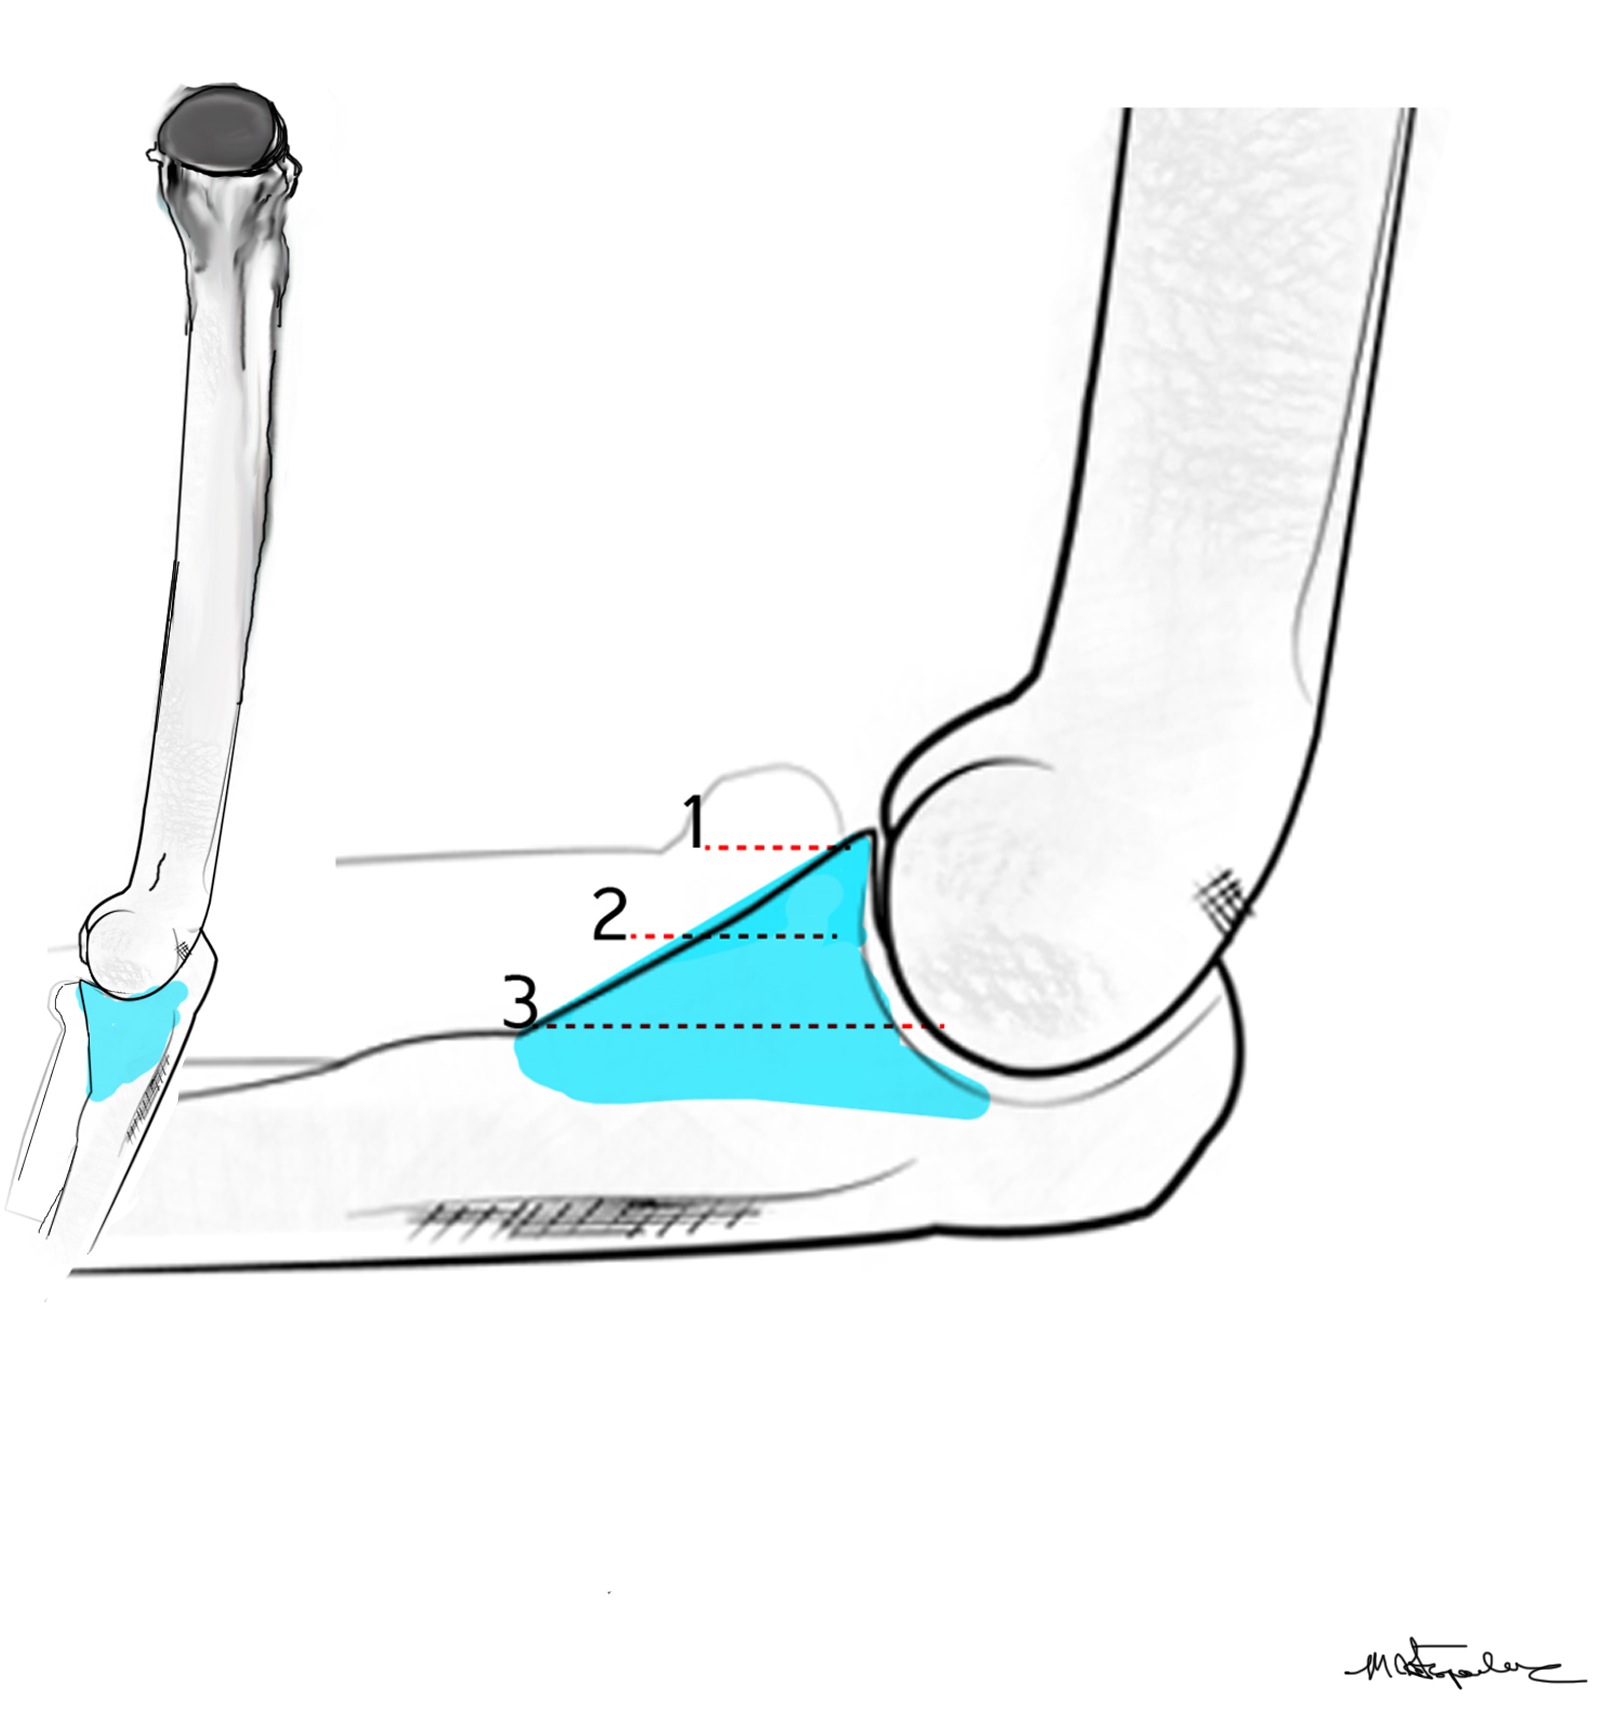

The coronoid is the most important portion of ulno-humeral articulation

Reasons

1. Provides anterior buttress

2. Anterior capsule and brachialis attach to coronoid

2. Anterior band of the MCL attaches to it

- distally and medially on sublime tubercle